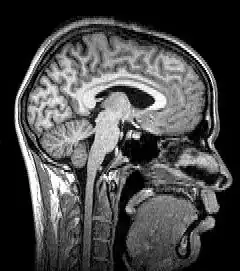

Para-sagittal MRI of the head in a patient with benign familial macrocephaly

Structural magnetic resonance imaging (structural MRI) of a head, from top to base of the skull

Sagittal MRI slice at the midline